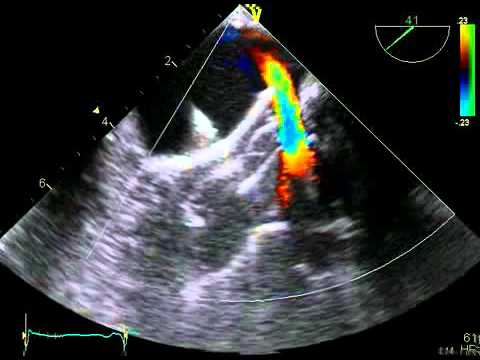

Video 16.7.1

Video 16.7.1 Guidance of transseptal puncture.

Video 16.7.2

Video 16.7.2 Guidance of transseptal puncture.